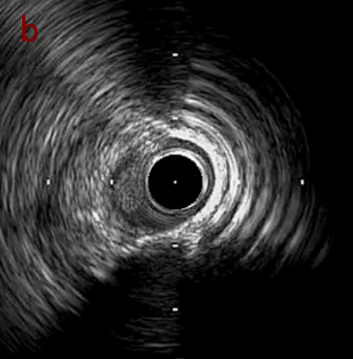

IVUS imaging

IVUSでは8時方向からPD枝がはいいてくる。

PreのIVUSではaの部位のみlipid plaqueを認め削ることでdistal embolismのリスクがあり、そのほかは270度の偏心性石灰化であるがwire biasは良好。

IVUS imaging after low speed 3回

OAS low speedによる引きのsandingを3回行いIVUSを確認するとa-cでは心筋側側へのOASによる良好なbias変化と、それに伴いdの健常側への危険なbias変化を認めた。